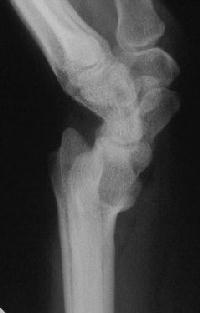

Right side, postop.